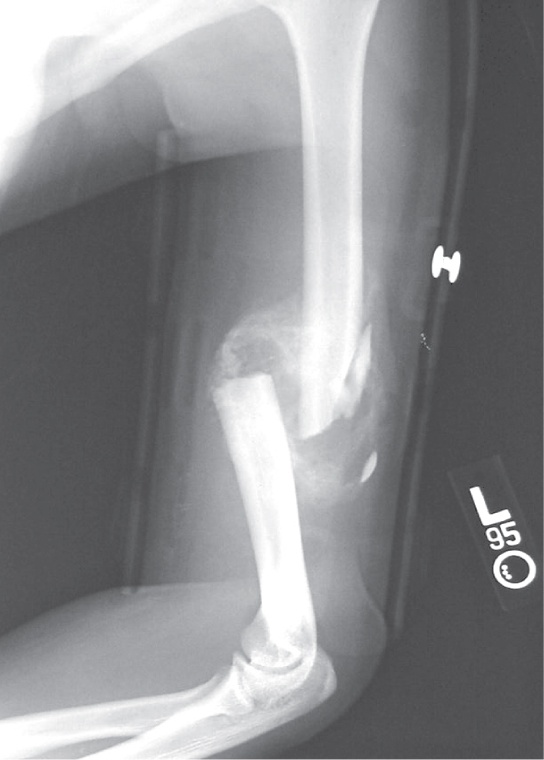

Photo shows an X-ray of a broken humerus—the bone in the upper arm.

After this bone is set, a callus will knit the two ends together. (credit: Bill Rhodes)